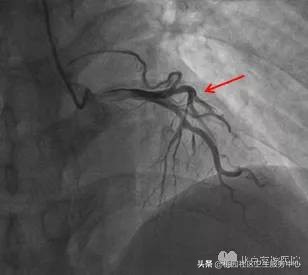

患者症状持续不缓解,行急诊冠脉造影检查,结果如图3:左前降支中段弥漫性狭窄100%完全闭塞,TIMI 0级,行PCI治疗后,LAD前向血流恢复至TIMI 3级,如图4;术后复查心电图,相应导联ST-T改变恢复正常,如图5。

图3:左前降支中段弥漫性狭窄100%完全闭塞,TIMI 0级

图4:LAD-PCI术后,LAD前向血流恢复至TIMI 3级